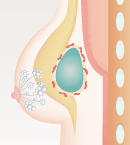

多くの場合、ヒアルロン酸を注入すると体は異物が入ってきたと捉えるので、コラーゲン線維の被膜で閉じ込めようとします。しかし、これは正常な生体反応。通常なら、被膜の薄いうちに体内の酵素成分がヒアルロン酸を分解、吸収されてなくなります。しかし、何らかの理由で分解されるより前に厚い被膜ができてしまった場合、しこりとして残ってしまうのです。

- 通常の経過

- 体内の酵素が少しずつ分解

- 分解後、吸収されてなくなる